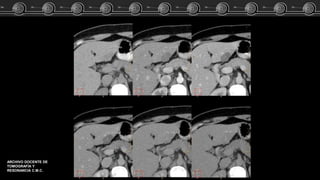

Adenoma, Hemangioma óHNF?? Caso Clínico Fem de 83 años…. El estudio TC demostró lesión focal a nivel del lóbulo izquierdo del higado. ARCHIVO DOCENTE DE TOMOGRAFÍA Y RESONANCIA C.M.C.